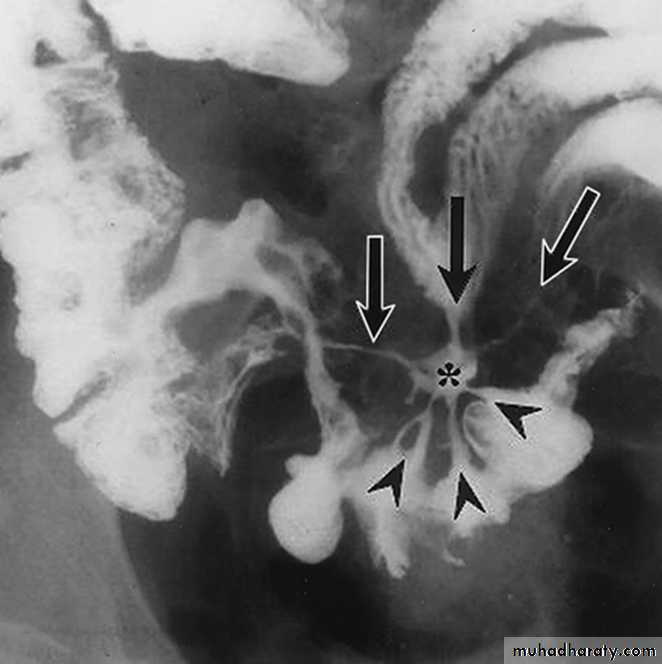

Crohns Disease :

• Crohn disease remains idiopathic• Radiographic features

• The characteristic of Crohns disease is the

• presence of :

• _skip lesions

• _multiple discrete ulcers.

• _The frequency with which various parts of the gastrointestinal tract are affected varies widely :

• *small bowel: 70-80%

• *small and large bowel: 50%

• *large bowel only: 15-20%

Radiological finding of CD in BA follow through :

• _Multiple mucosal ulcers aphthous ulcers.• _Transmural ulcer (Rose thorn appearance )

• _longitudinal fissures

• _Multiple skip lesions

• _when severe leads to cobblestone appearance

• _May lead to sinus tracts and fistulae

• _widely separated loops of bowel due to fibro-fatty proliferation

• _Thickened folds due to edema.

• _Pseudo diverticula formation: due to contraction at the site of ulcer with ballooning of the opposite site.